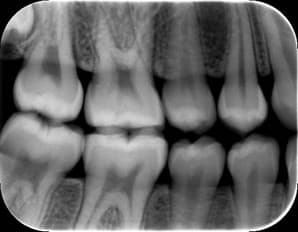

Show the upper and lower teeth in one area of the mouth to detect cavities between teeth and check bone levels. They’re commonly taken during routine checkups to help monitor your oral health over time.